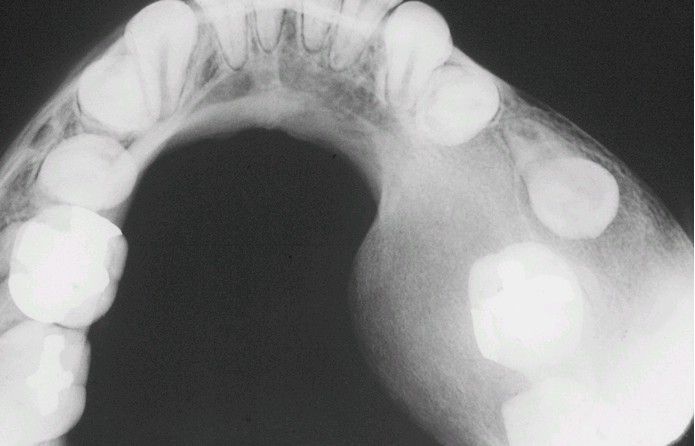

Occlusal radiograph showing localized expansion of the mandible and the “ground-glass” radiographic appearance. The margins of the lesion are not well defined and blend into the adjacent bone